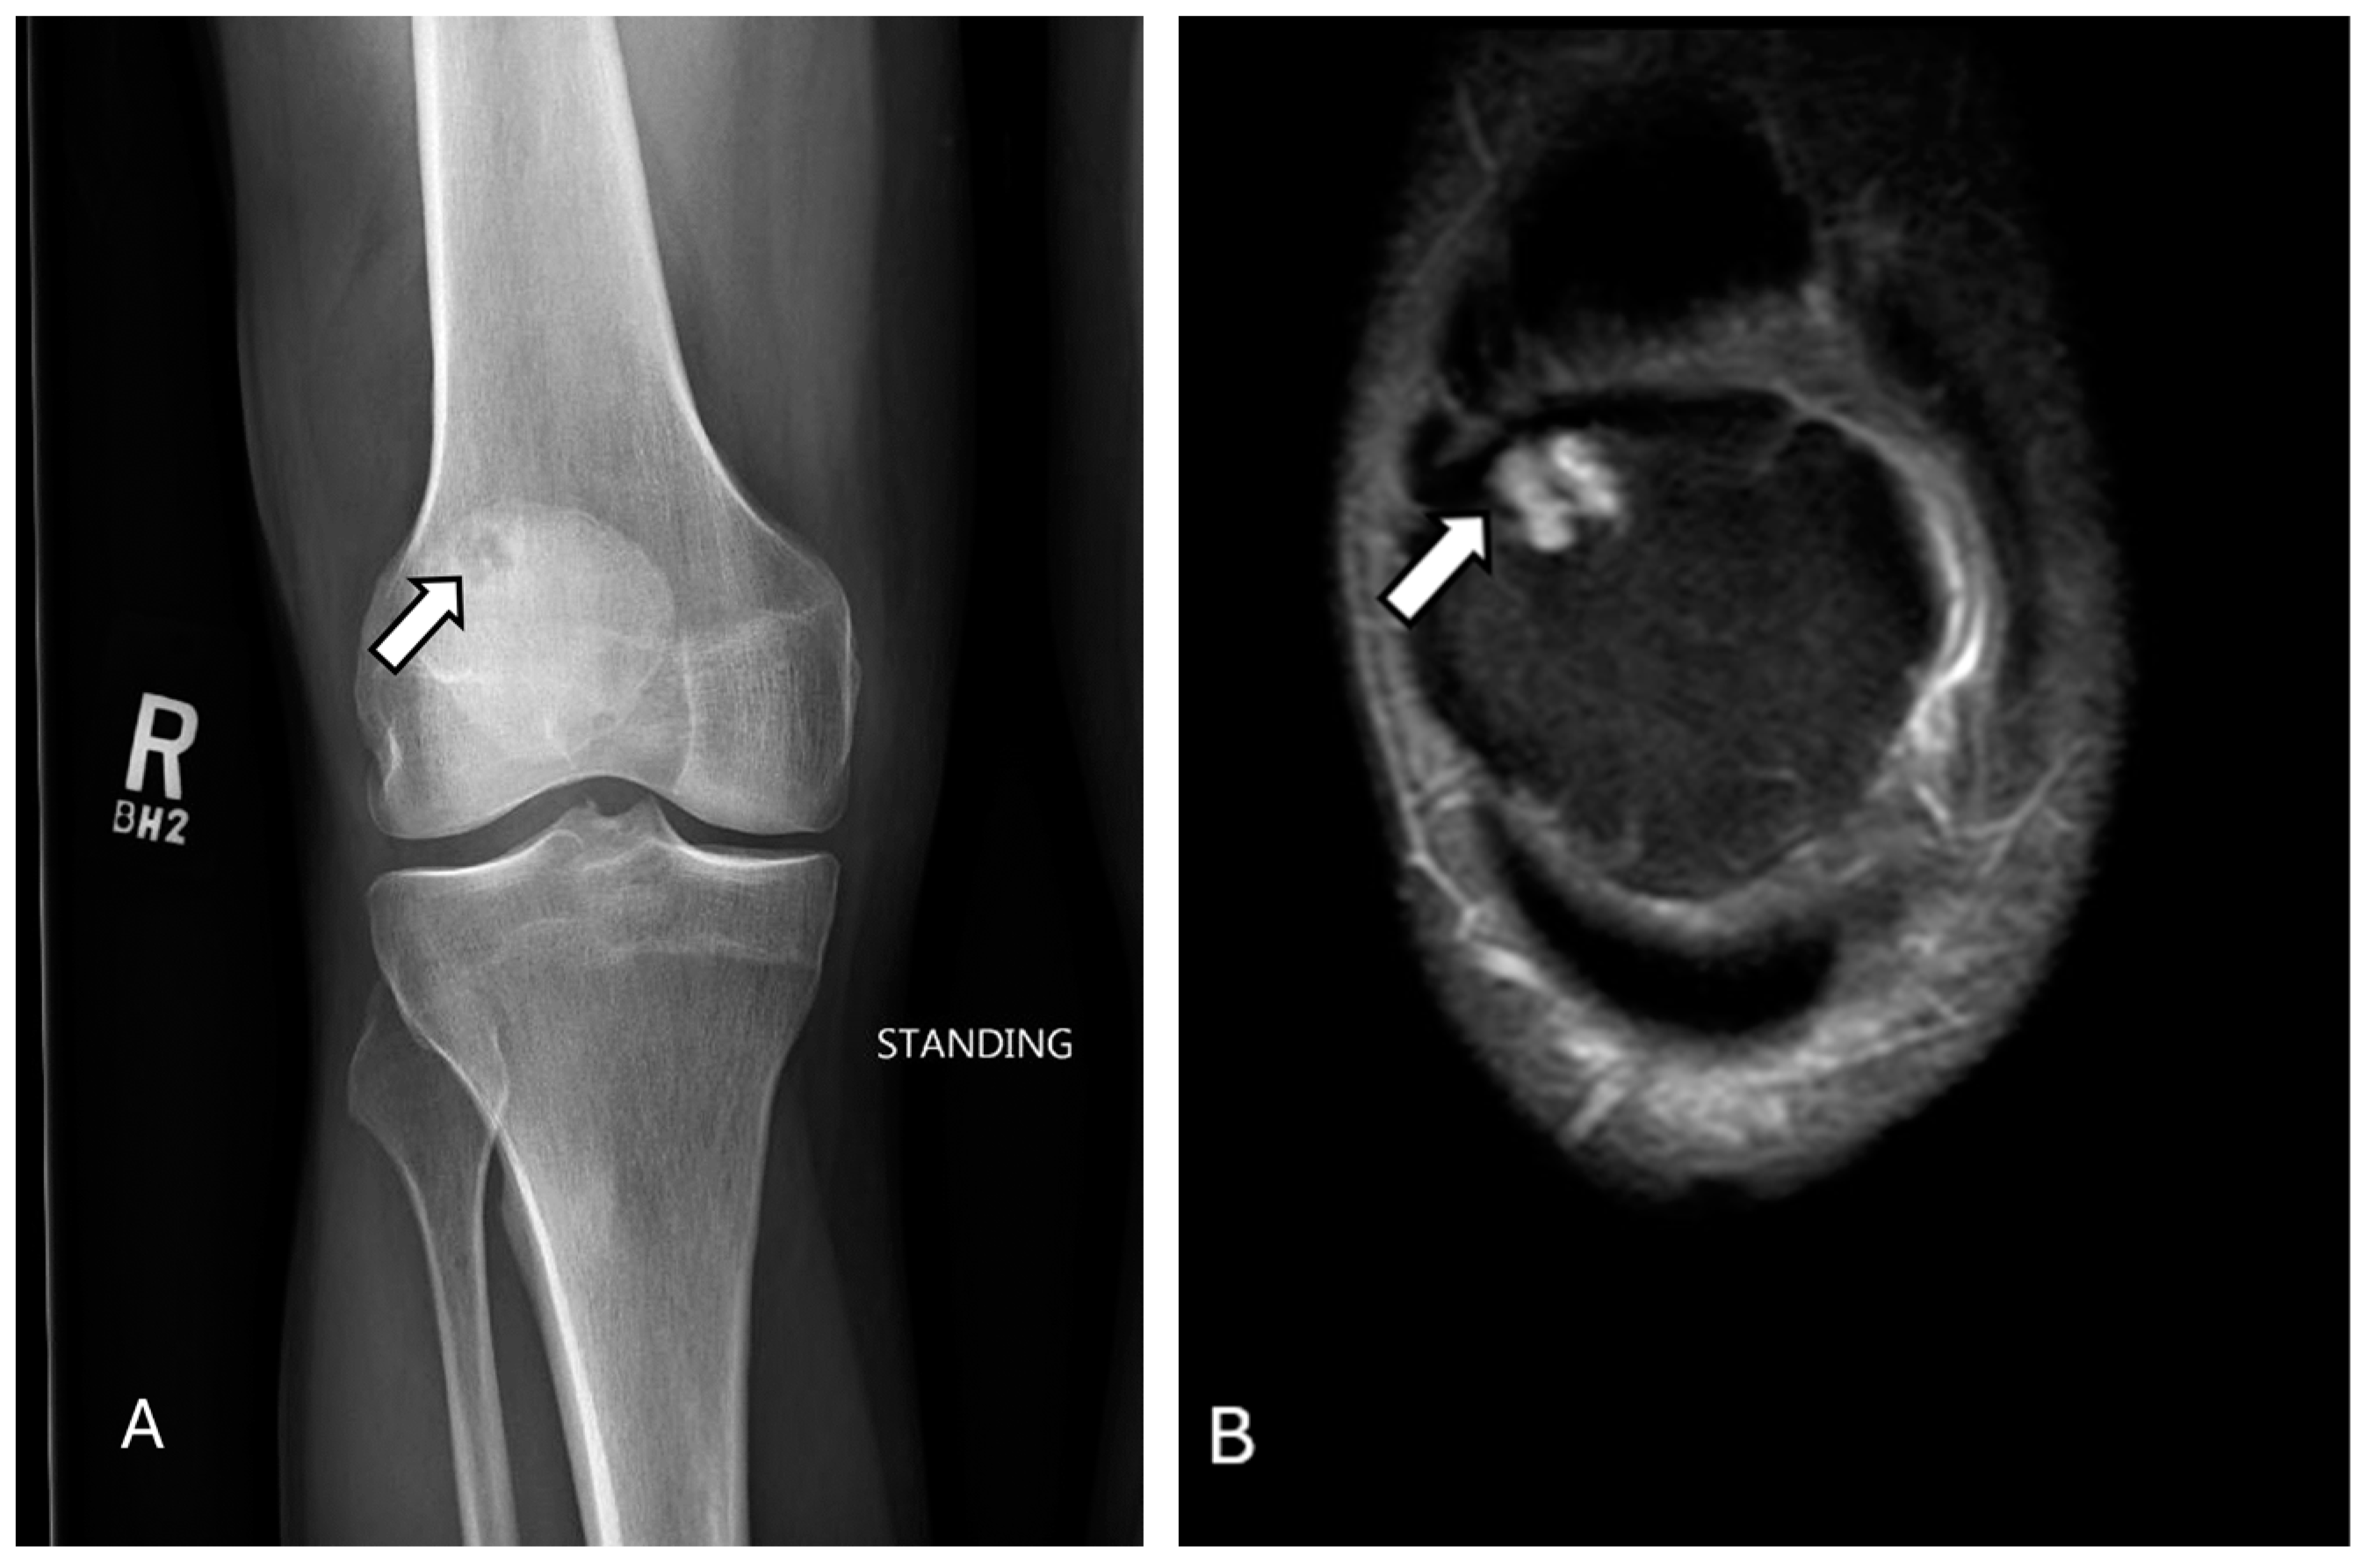

2.1. Bipartite/Multipartite Patella